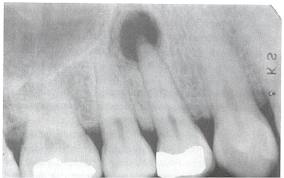

Fogászati és szájhigiénés szűrés

Általánosan elmondható, hogy már a gyermekvállalás tervezésének szakaszában ajánlott a fogászati státusz rendbetétele és az ínybetegségek kezelése. Ez azért is fontos, mert a szűrés során pl. fogászati röntgenvizsgálatra is szükség lehet. Ami viszonylag alacsony sugárterheléssel jár, azonban a terhesség alatt még így sem javasolt. Emellett a várandósság során majdan bekövetkező hormonális változások fogékonyabbá tehetnek a fogínybetegségekre.

Fogászati góckutatás

A gócok olyan, többnyire letokoltan elhelyezkedő baktériumok a szervezet különböző pontjain, amelyek az immunrendszertől elzártan találhatóak. Ezért annak ellenére, hogy jelenlétük immunválaszt indukál, az immunrendszer mégsem tud megküzdeni velük. Habár a túlzott immunválasz elsősorban a szájban koncentrálódik, mégis fokozott gyulladásos mechanizmusok indulhatnak el a szervezet más területén. Végeredményként pedig ez a folyamatosan fennálló és állandósult gyulladásos immunreakció különböző, az általános közérzetet és az életminőségét rontó tünetekhez vezethet.

Bizonyított, hogy az immunrendszer túlzott reakciókészsége növeli a meddőség, a vetélés és a sikertelen beágyazódás kockázatát is. Emellett a női meddőség gyakori okai, mint az endometriózis vagy a PCOS szintén összefüggésbe hozhatók a periodontális betegségekkel. A fogágy gyulladása továbbá növelheti a koraszülés rizikóját, valamint hatással lehet az újszülött súlyára is.

Fogászati góc alatt a szájüregben vagy az állkapocs csontállományában keletkezett, hosszú ideje jelenlévő, betokozódott, krónikus gyulladást értjük. Bár a szervezet a kórokozókkal teli fogászati gócot megkísérli lezárni és elválasztani a test többi részétől, ennek ellenére a gócból folyamatosan távoznak baktériumok vagy baktérium törmelékek a véráramba. Így a szervezet egy másik pontján azután újabb gyulladást idézhetnek elő.